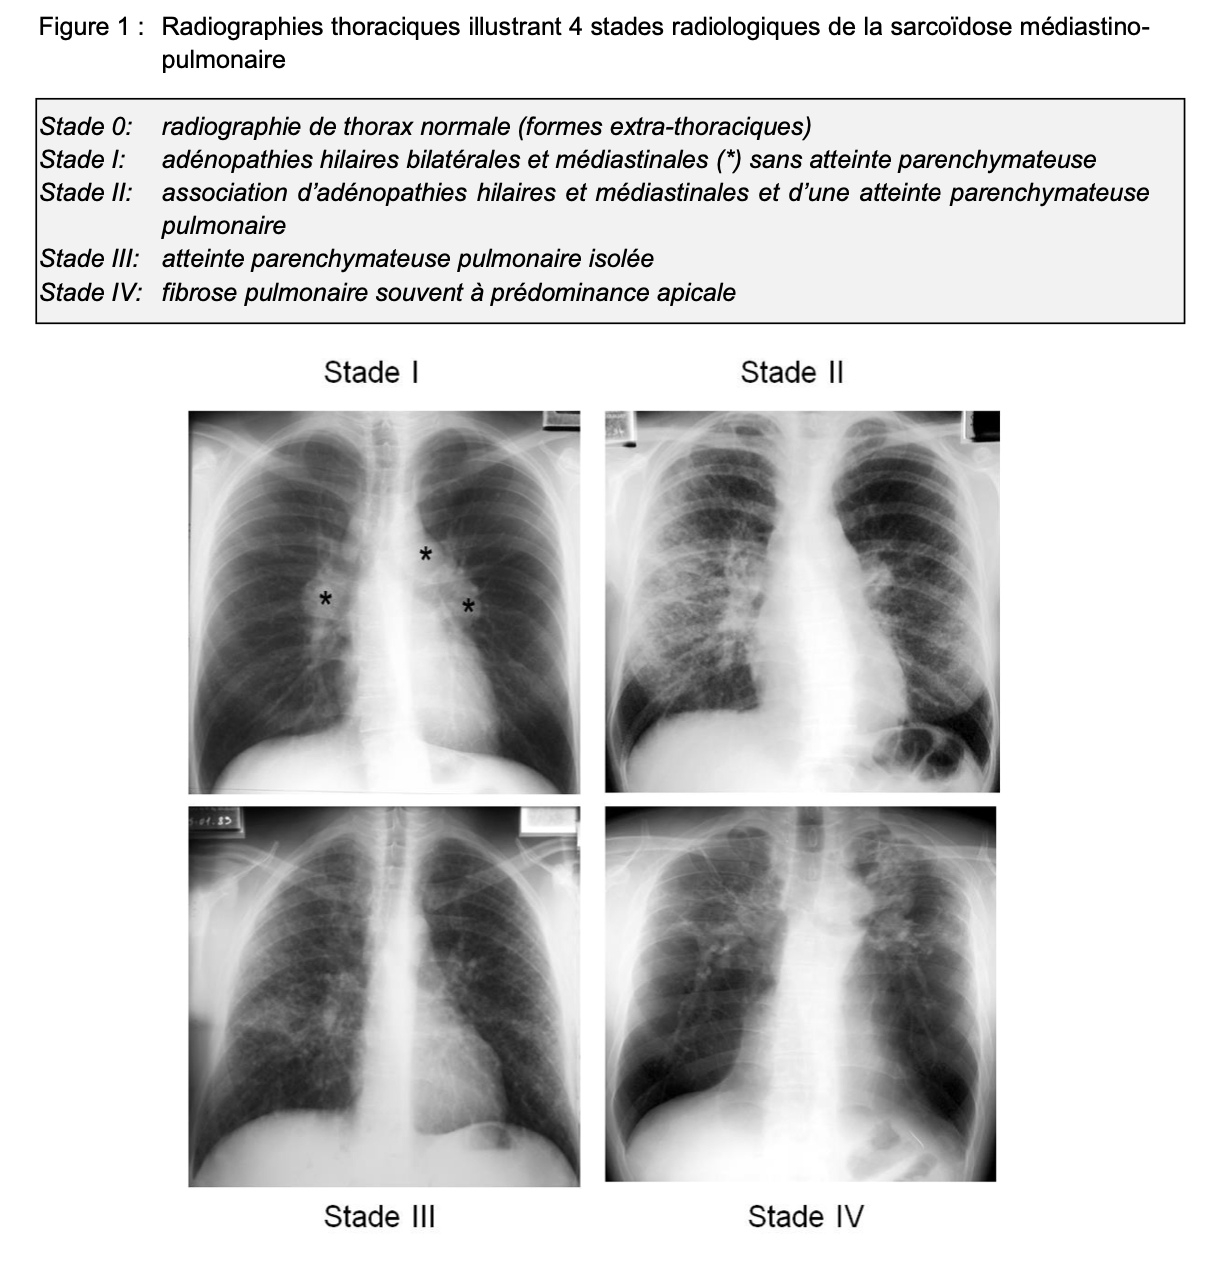

Stade radiologique de la sarcoidose =

=> Figure 1

Caractéristiques des adénopathies intrathoracique de la sarcoidose :

▪ hilaires, bilatérales, symétriques, homogènes et non compressives (dans 95% des cas)

▪ souvent médiastinales, notamment latéro-trachéales droites (70% des cas),

▪ plus rarement elles peuvent être asymétriques ou compressives et doivent faire éliminer formellement un diagnostic alternatif,

▪ peuvent se calcifier dans les formes très prolongées.

Caractérisitques de l’atteinte parenchymateuse pulmonaire :

▪ réalise un aspect micronodulaire diffus

▪ prédomine dans les parties moyennes et supérieures des champs pulmonaires

➔ Le contraste entre l’importance de l’atteinte radiographique pulmonaire et la discrétion de la symptomatologie fonctionnelle respiratoire est habituel et constitue un élément en faveur du diagnostic de sarcoïdose.